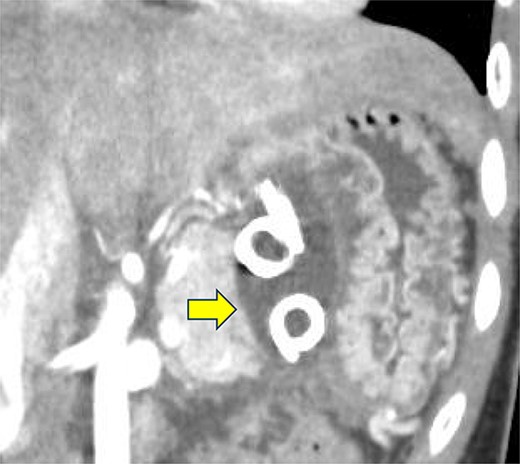

On the fifth day, the ascitic fluid increased in volume, and an open distal pancreatectomy was considered. However, her condition was stable. CT-guided abdominal drainage was performed, and a 10 Fr drainage tube was inserted for peritoneal lavage (Fig. 4). EUS-guided transgastric drainage of the pseudocyst in the omental bursa was performed. The pseudocyst was punctured; a balloon was dilated through the posterior wall of the stomach (Fig. 5a–c), and three tube stents of 7 Fr were implanted (Fig. 5d). The Amy and P-Amy levels in ascites were 9429 and 8877 IU/L, respectively; then, peritoneal lavage was performed daily. On the 12th day, contrast-enhanced CT revealed reduced pseudocyst size (Fig. 6). The patient was discharged on the 16th day (Fig. 7). Three years later, the patient is living her daily life without any complications.

Contrast-enhanced CT on the 12th day. The pseudocyst in the omental bursa had shrunk. The arrow indicates the pseudocyst.